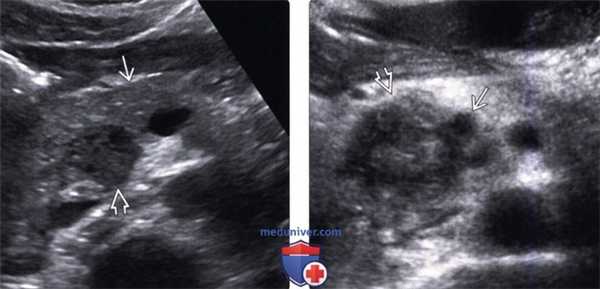

(Левый) На поперечном УЗ срезе брюшной полости в головке поджелудочной железы определяется округлое объемное образование, гипоэхогенное по сравнению с нормальной тканью поджелудочной железы.

(Правый) На поперечном УЗ срезе брюшной полости выявляется инфильтративное гетерогенное объемное образование головки поджелудочной железы, охватывающее верхнюю брыжеечную вену.